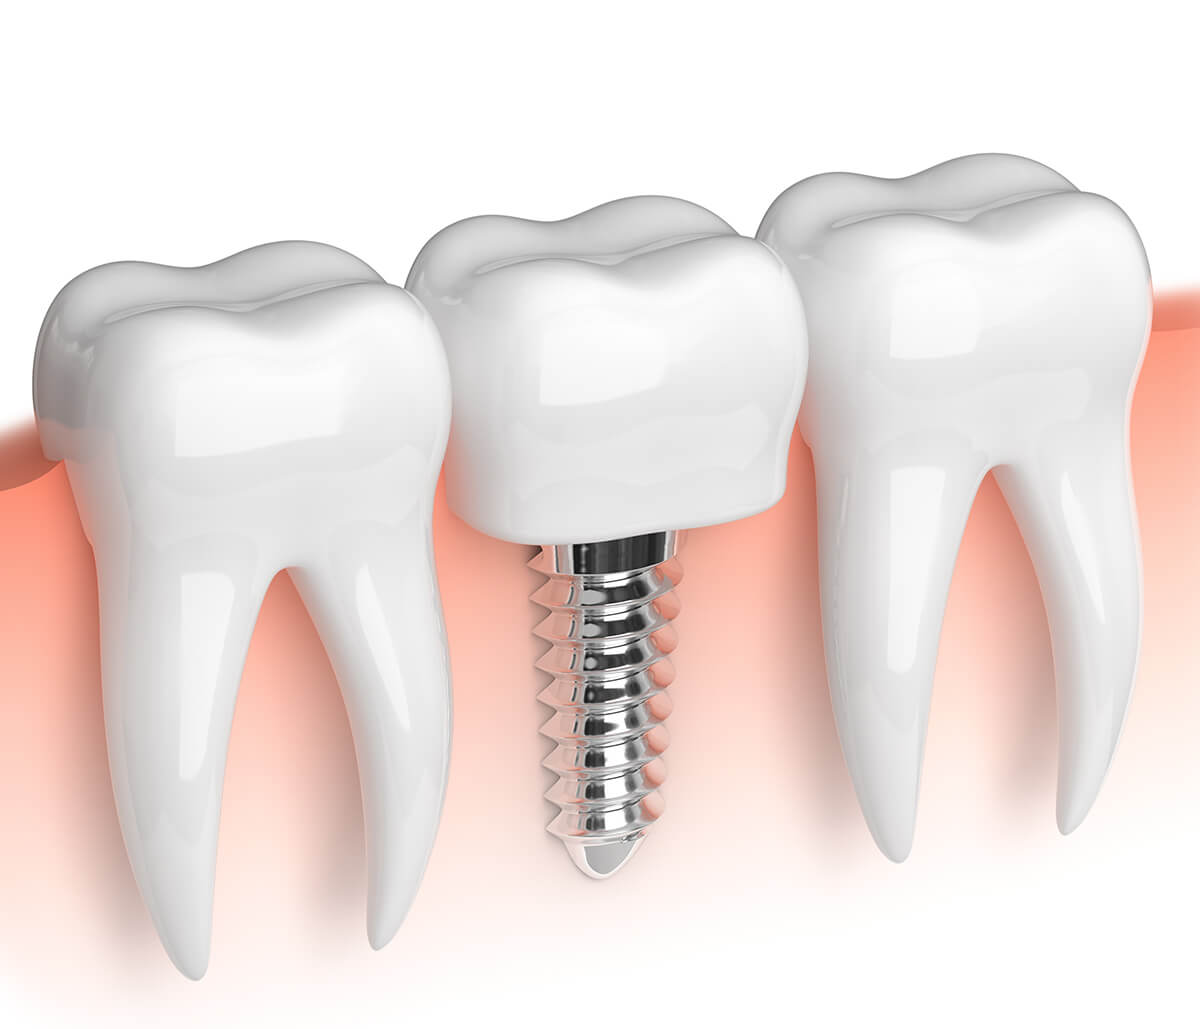

Patients faced with tooth loss in the Daly City, California area are often interested in discussing the benefits of solutions such as dental implants. Dental implants allow a patient to replace one or more teeth in the smile with the help of an experienced dentist. These restorations feel, look, and function as natural teeth.

There are various factors that need to be taken into consideration when it comes to determining the cost of a dental implant. The cost of a dental implant in Daly City and San Mateo County ranges between $2500 and $3500. We offer the dental implant placement, abutment, and dental crown for restoring a single tooth. Fortunately, patients who have dental insurance may be able to reduce these costs dramatically, reducing the out-of-pocket expenses of this and other procedures patients might need at our dental practice.

Before moving forward with placing and restoring a dental implant, patients need to make sure they are viable candidates for implants. They are also patients who have not experienced significant bone resorption, or bone loss, in the jaw. To place a dental implant, it requires sufficient bone structure where the implant is surgically placed. If there is not enough bone, the treatment will be unsuccessful, and patients may need to consider alternative options such as bone or block grafting.

It takes a few hours to place a dental implant and a temporary crown can be provided on the same visit. Many weeks are needed to wait out the process of osseointegration, where the jawbone wraps around the implant to hold it in place. The entire treatment is finished in four to six months.